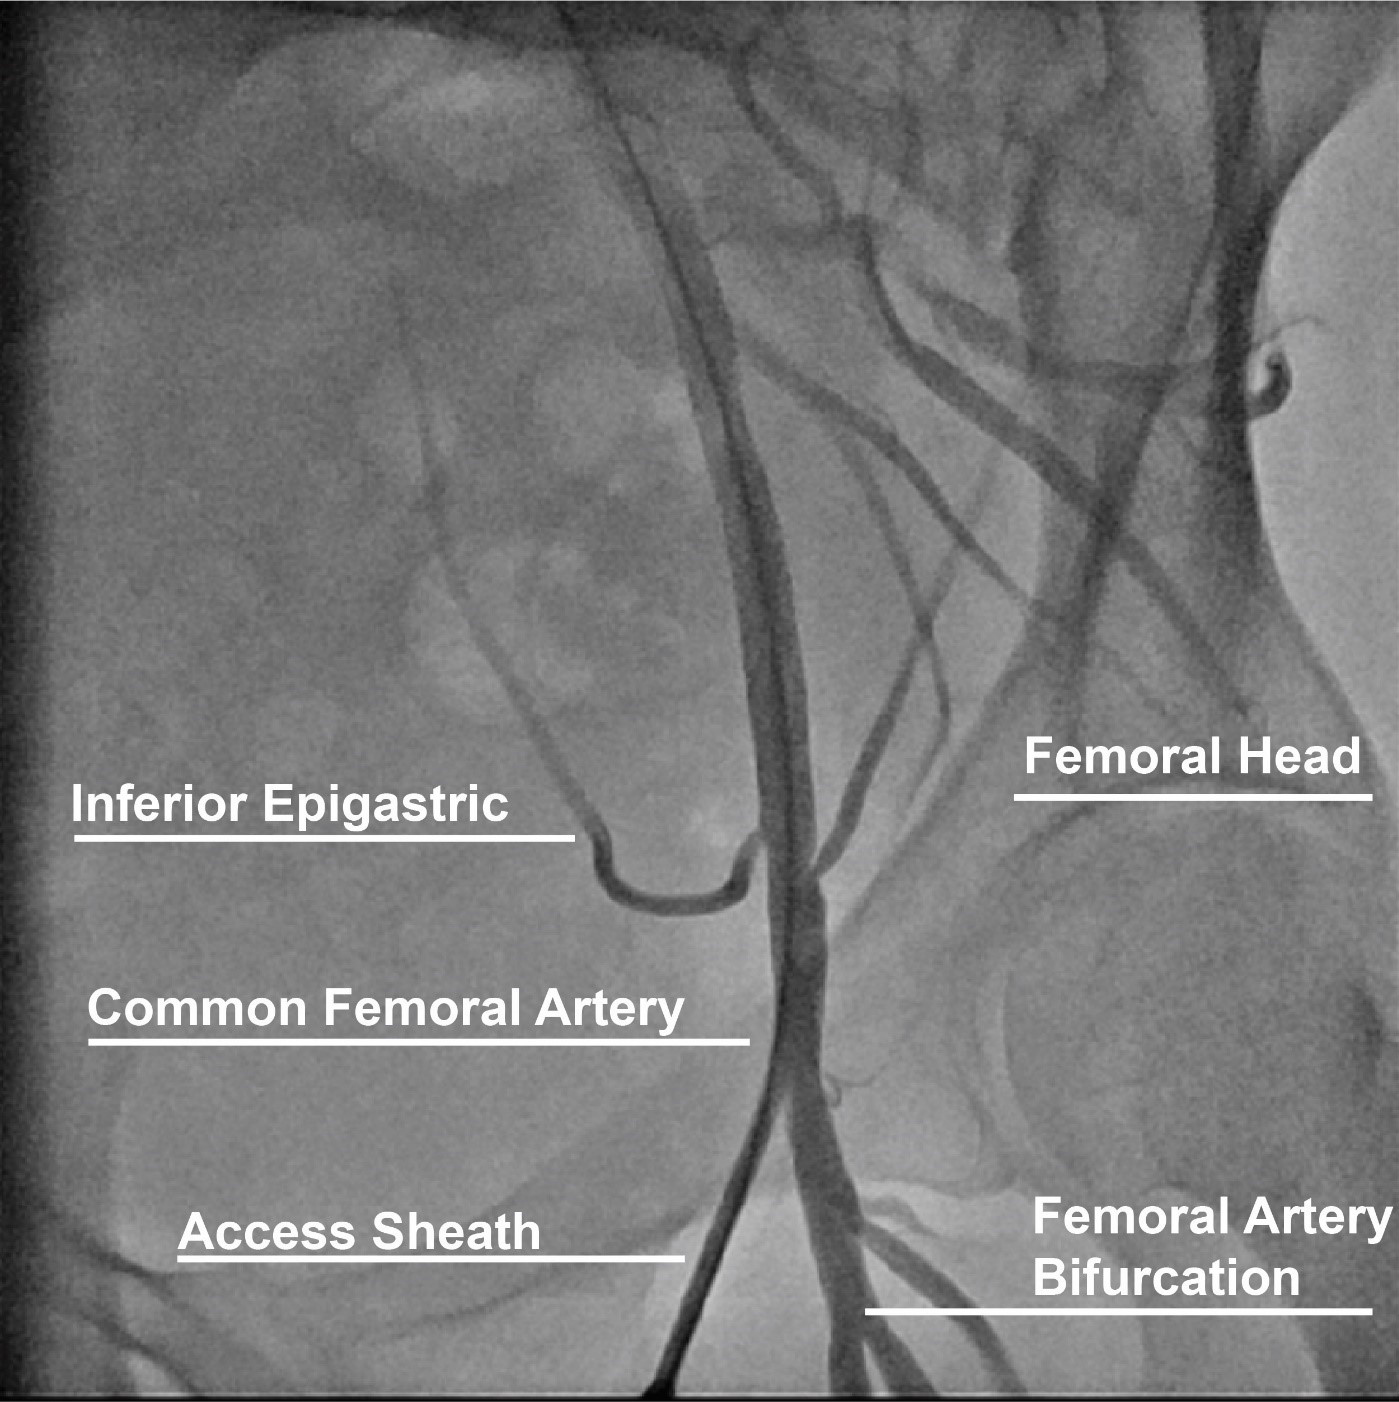

The CFA originates from the external iliac artery and crosses under the inguinal ligament and branches into the superficial (SFA) and profunda (PFA) femoral arteries distally (Fig. 1) [11]. The large caliber and ability to compress the artery over the femoral head of the CFA make this arterial anatomical site the preferred for procedures requiring femoral access. Successful CFA access is established when the sheath is inserted into the CFA above the bifurcation of the SFA and PFA and below the inferior epigastric branch in an area compressible against the femoral head. Anatomical landmarks to maximize CFA access include finding the anterior superior iliac spine laterally and the symphysis pubis as a landmark for the inguinal ligament and obtaining access 2–3 centimeters below the midpoint between these landmarks. However, anatomical variations such as high bifurcation and obesity diminish the reproducibility and accuracy of this technique [12]. Low access increases the risk for bleeding and hematoma due to lack of a compressible site, and pseudoaneurysm [13, 14]. High access (above the inguinal ligament) increases the risk of a retroperitoneal bleed, which is associated with a 3-fold increase in mortality and a 5-fold increase in adverse outcomes [15]. Other predictors of retroperitoneal bleeding include low body weight, female sex, larger sheath size, and use of glycoprotein IIb/IIIa inhibitors [16, 17]. Therefore, adjunctive techniques to accurately access the CFA such as fluoroscopy and ultrasound have been implemented to contemporary femoral access techniques and will be discussed in the following sections.

Fig. 1.Anatomical landmarks for femoral access.